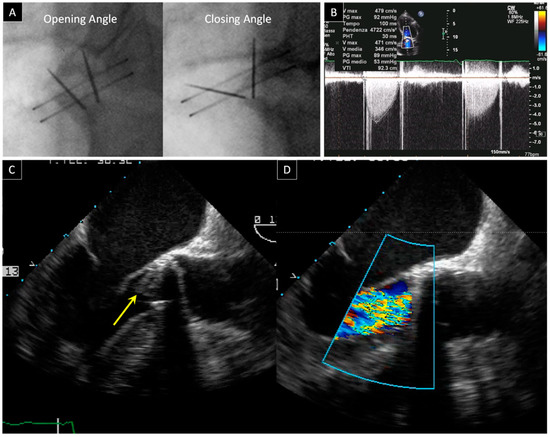

2. Prosthetic Valve Obstruction

2.1. Prosthetic Mitral Valve Obstruction